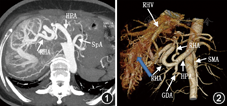

入院后经会诊于2014年12月3日行冠状动脉造影未见明显狭窄。右心导管术:外周血氧饱和度100%,上腔静脉氧71%,主肺动脉氧84%,右心房氧83%,右心室氧84%,右心室射血分数59%,肺动脉楔压15 mmHg,心输出量11.8 L/min(成年人正常值5~6 L/min),心脏指数7.7 L·min-1·m-2(成年人正常值3.0~3.5 L·min-1·m-2),左向右分流比率1.8(正常值为1.0)。鉴于患者上腔静脉和右心房血液氧饱和度相差大,且心脏指数、左向右分流比率均增高,需寻找左向右的异常分流的部位。因当时未测量下腔静脉血氧饱和度,超声与胸部血管CT检查均未发现有房室间隔缺损及异位肺静脉引流,故疑有下腔静脉异位引流。2015年4月20日上腹部血管CT未见明显粗大的肝动脉肝静脉直接相通征象,但动脉期肝静脉即显影,肝动脉及肝静脉异常增粗,符合肝动脉-肝静脉瘘(hepatic arteriovenous fistula, HAVF)(图1,图2)。经股动脉行肝血管造影见肝左动脉起自胃左动脉,胃左动脉及肝总动脉明显增粗,扭曲明显,动脉期可见肝静脉提早显影,肝内见弥漫性HAVF,以肝右动脉肝静脉瘘为主,由肝固有动脉、肝左动脉及右膈动脉供血。用无水酒精和适量明胶海绵颗粒制成的乳剂栓塞肝右动脉分支,栓塞后造影见肝右叶HAVF大部消失(图3)。术后患者偶感胸闷心悸明显,劳累后加剧,于2015年6月30日复查肝血管造影见双侧膈动脉和肝总动脉均增粗、扭曲,仍有弥漫性HAVF,由肝动脉及膈动脉供血,肠系膜上动脉造影见动脉盗血现象(图4)。分别采用浓度为25%和28%的正丁基-2-氰基丙烯酸盐进行栓塞肝右动脉两个分支,栓塞后肝右动脉肝静脉瘘消失,肝左动脉还存在动静脉分流,术后胸闷心悸症状好转。术后半年复查超声心动图示左、右心房较前明显缩小:LVEF 71%,LAD 38 mm,RAD 31 mm,LVDd 54 mm,RVDd 33 mm,肺动脉收缩压33 mmHg。术后1年复查腹部血管CT:肝动静脉瘘未见明显进展,心电图在正常范围内,胸片心影较术前缩小,心胸比0.62。在1年的随访中患者未诉明显胸闷心悸不适,稍有右上腹间断性疼痛不适,口服止痛药有效,现已很少服用。